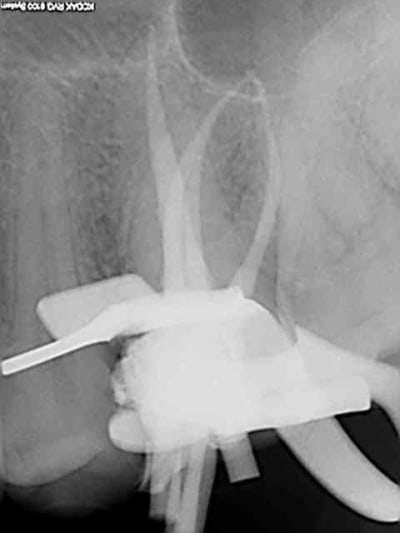

Et une de plus !

R19 vxiysf - Eugenol

R20 kboz6l - Eugenol

C'est pas de la frime hein, mais ca fait plaisir d'avoir trouvé ENFIN une technique rapide et reproductible sans casse. (enfin presque il y a dans le tas un micro morceau de R25 pas loin de l'apex )